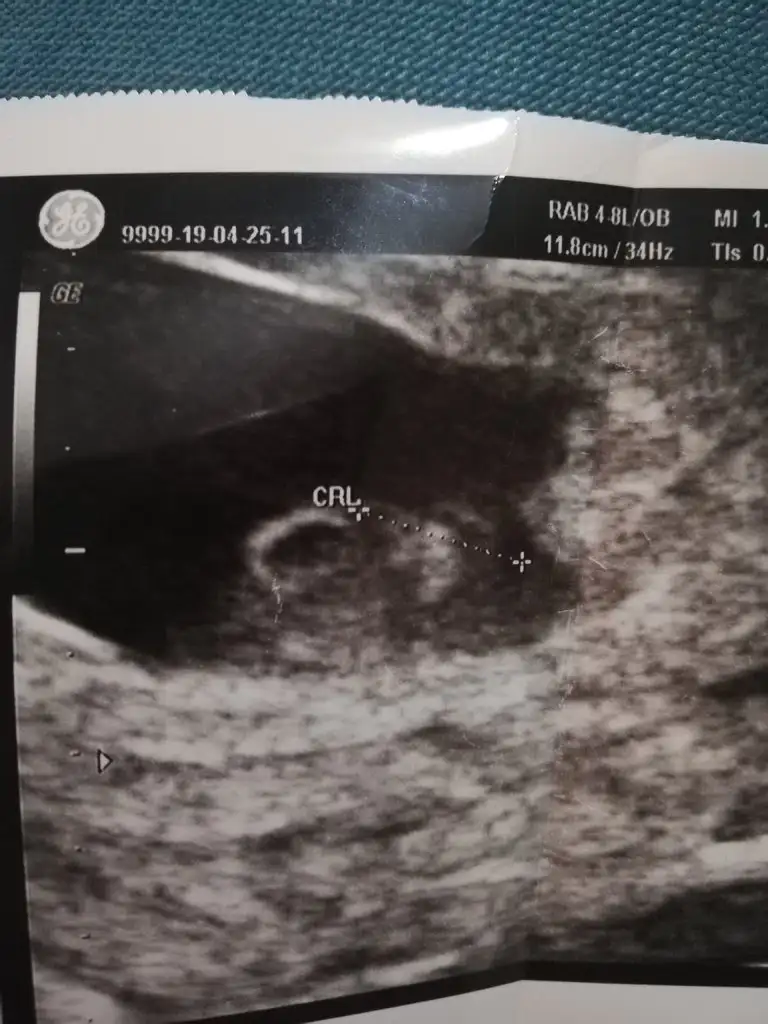

İnşallahhh kuzum durun size ultrason fotosunu atayım kafa önde çıktı sanırım oda bize bakıyordu 😁

IMG_20190430_223250.webp